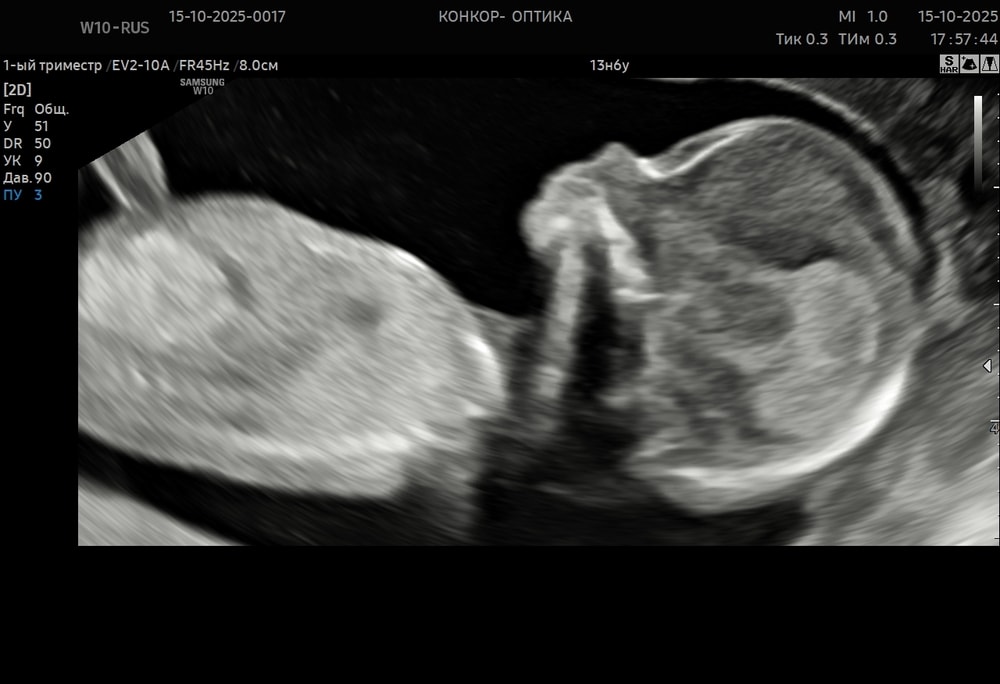

Пошли сегодня на УЗИ из-за очередных переживаний: 3 дня прострелов в промежности. А по скринингу хорион на 1 см до зева. Начиталась, распереживалась, пошла на УЗИ в нормальную клинику с шикарным аппаратом.

Через живот посмотреть не получилось, потому что малышок удобно устроился вниз головой. Внутри всё пошло хорошо. Мы очень удивились, увидев шевеления. Он так смешно отвернулся. Лежал-лежал, а потом резко попой к датчику😅 пуповину между ног зажал, лежит удобненько. Носик красивый... Муж весь приём на видео записал от удивления 😂 врач потом ещё тоже прислала фото и видео) устроили фотосессию нашему солнышку.

А расстояние увеличилось до 1.9 см от зева. Так что может из-за этого и тянуло